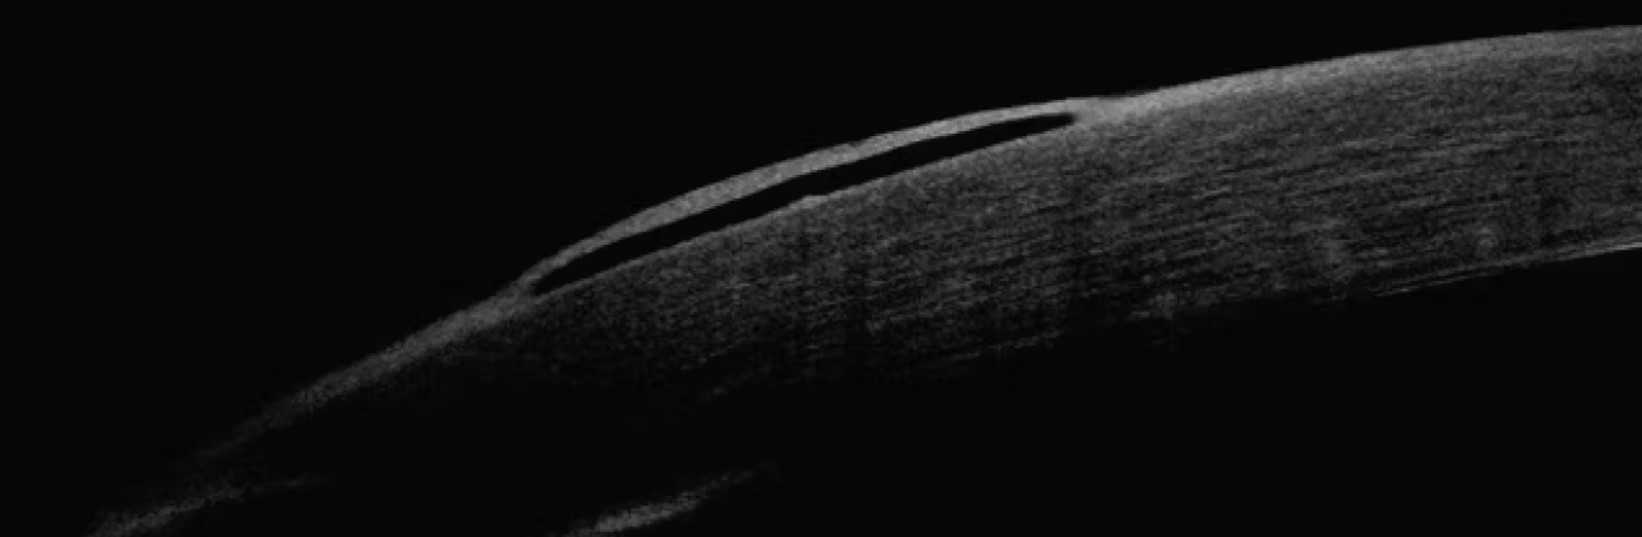

3단계 상피부종상태가되면,

각막의 내피 기능 부전으로 인한 각막기질의 부종이 심해지면서, 각막 전층이 부어,

각막상피까지 붓게되는 상태를 의미합니다.

이때는 각막 상피에서 미세한 상피내 소낭포(epithelial microcyst)가 관찰되며,

이가 합쳐져서 낭포(bulla, cyst)가 발생하고, 이것이 터지면 이물감과 통증을 유발합니다.